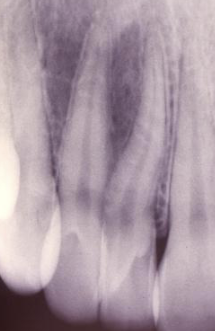

DGI radiographic presentation

bulbous crown, cervical constriction, pulp obliteration varies, expanded pulp = shell teeth

a hereditary condition of dentin in the absence of any systemic disease (opalescent dentin), AD, genetic mutation is DIFFERENT from osteogenesis imperfecta

dentinogenesis imperfects (DGI)

DGI-II clinical presentation

isolated opalescent teeth, most common

affects both dentition, steel-grey/ translucent/ opalescent crowns, brittle enamel

DGI